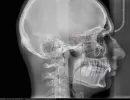

Я хочу поставить себе брекет-систему. После осмотра врач сказала, что обязательно нужно удалять зубы мудрости и далее ходить в брекетах минимум полтора года. У меня в наличии имеются рентгеновские снимки и заключение врача. Хотел бы понять, не разводят ли меня на ненужное лечение.

Хотел бы понять насколько это действительно так? Обязательно ли удалять зубы мудрости и обязательно ли ходить в брекетах столько времени?

Удаление восьмых зубов имеет место. Для 38-го отсутствует антагонист, а 18-й и 48-й для симметричности зубных рядов.